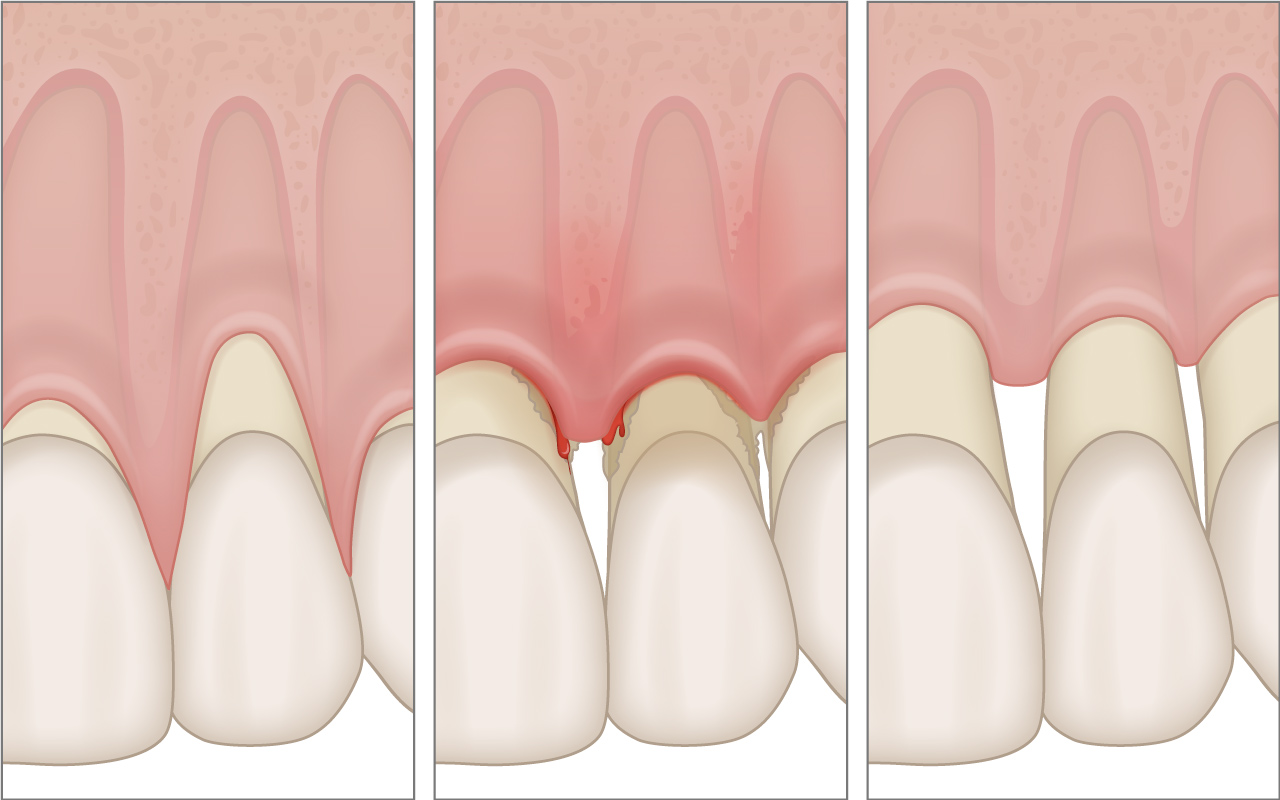

Mehr ...Zahnfleischrückgang kann unterschiedliche Gründe haben und häufig auf der Aussenseite des Gebisses oder bei Parodontitis und nach ihrer Behandlung auch um den gesamten Zahn auftreten.

Zahnfleischrückgang bei der Parodontitis

Zahnfleischrückgang kann unterschiedliche Gründe haben und häufig auf der Aussenseite des Gebisses oder bei Parodontitis und nach ihrer Behandlung auch um den gesamten Zahn auftreten.

Als Zahnfleischrezession bezeichnet man grundsätzlich den Zahnfleischrückgang auf der Aussenseite des Gebisses. Betroffene erleiden in solchen Fällen keine zusätzliche Parodontitis.

Allerdings kann die Parodontitis im fortgeschrittenen Stadium auch zur Rückbildung des Zahnfleischrandes führen. Erst eine Untersuchung in der Zahnarztpraxis schafft bei Betroffenen Klarheit darüber, welche Ursache bei ihnen für den Zahnfleischrückgang verantwortlich ist.

Zusätzlich wird nach der Behandlung einer Parodontitis ein Zahnfleischrückgang beobachtet. Dieser ist in solchen Fällen jedoch gewünscht, da durch die Schrumpfung des Zahnfleischrandes die unerwünschten Zahnfleischtaschen reduziert werden können.